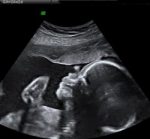

Rahim, yumurtalıklar ve doğmamış çocuk (fetus) gebelerde